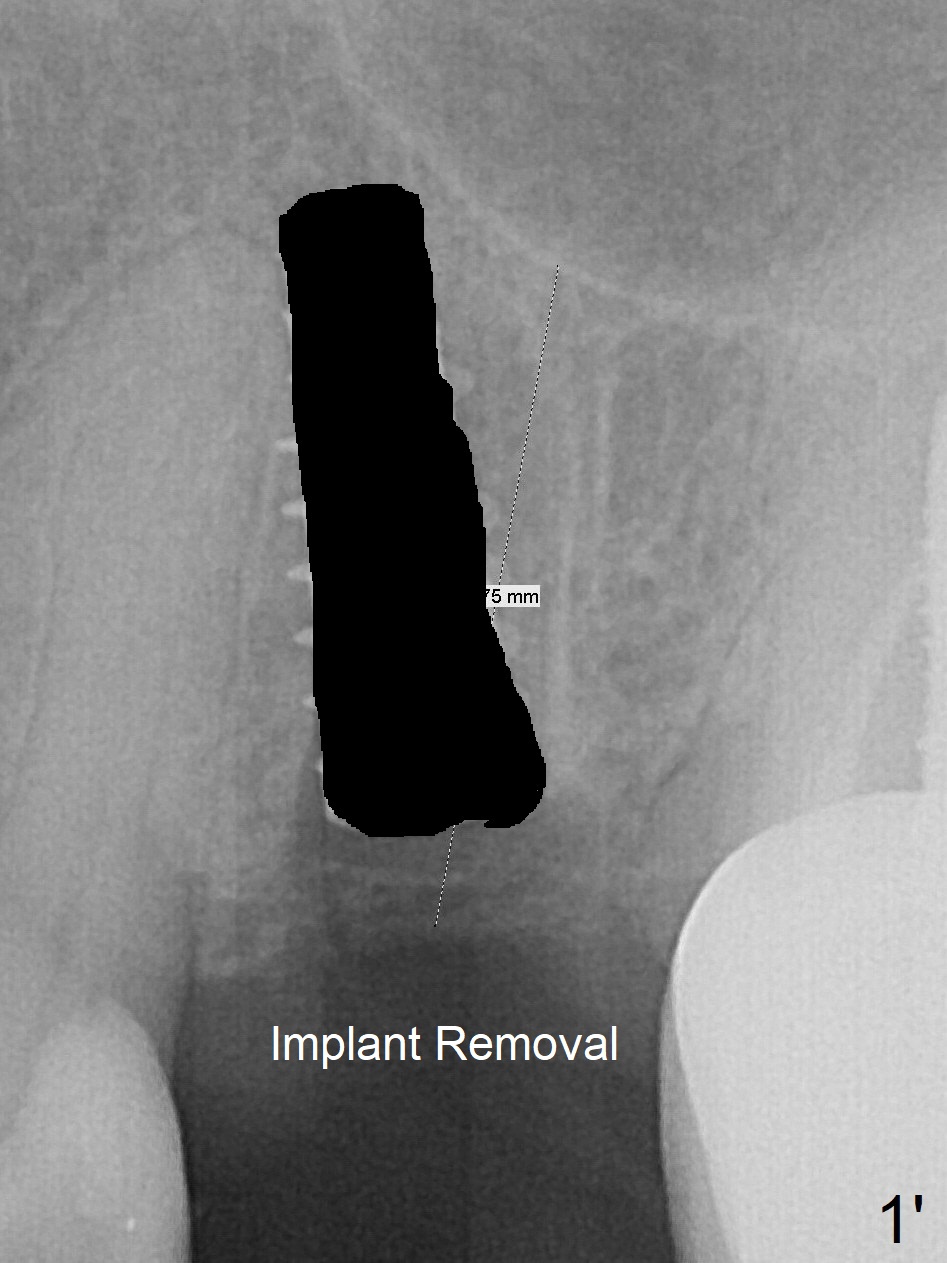

First, the implant is removed (Fig1'). Move the osteotomy distal by using Lindamann bur (Fig.1''). Remove the Lindamann bur (Fig.1'''). Reuse 3.3 m Magic Drill (Fig.1''''). After using Lindamann bur to move the osteotomy distal and reusing 3.3 mm drill, the trajectory of a 4.5x11 mm IBS dummy implant improves (Fig.2 with low stability).